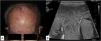

In our series, we wanted to highlight patient #2 (Fig. 1A) and patient #8 (Figs. 1B and 2) due to their presentation in atypical locations. Patient #2 presented with a tumor at the vertex and patient #8 with lesions at genital level. Specifically, the latter was diagnosed based on the presence of a massive edema in the scrotum occupying a large part of the subcutaneous cellular tissue (SCT). Despite an initial diagnosis of scrotal cellulitis (Fig. 1B), the patient's poor clinical evolution prompted an incisional biopsy (Fig. 2), which revealed diffuse infiltration of the dermis and subcutaneous tissue by a neoplasm composed of highly atypical B-cell lymphoid cells of medium to large size. The cells exhibited marked nuclear pleomorphism, abundant karyorrhexis, and a diffuse growth pattern arranged in loose, trabecular, and sheet-like formations.